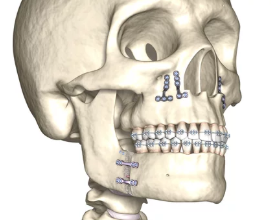

양악수술은 턱의 균형을 맞추고 기능적, 심미적인 문제를 해결하기 위해 이루어지는 복합적인 수술입니다. 수술 후에는 일정한 회복기간과 관리가 필요하며, 개인에 따라 차이가 있기는 하지만 일반적으로 몇 가지 공통적인 단계로 나누어집니다. 이 글에서는 양악수술 회복기간과 각 단계에서의 특징, 관리 방법을 폭넓게 알아보겠습니다.